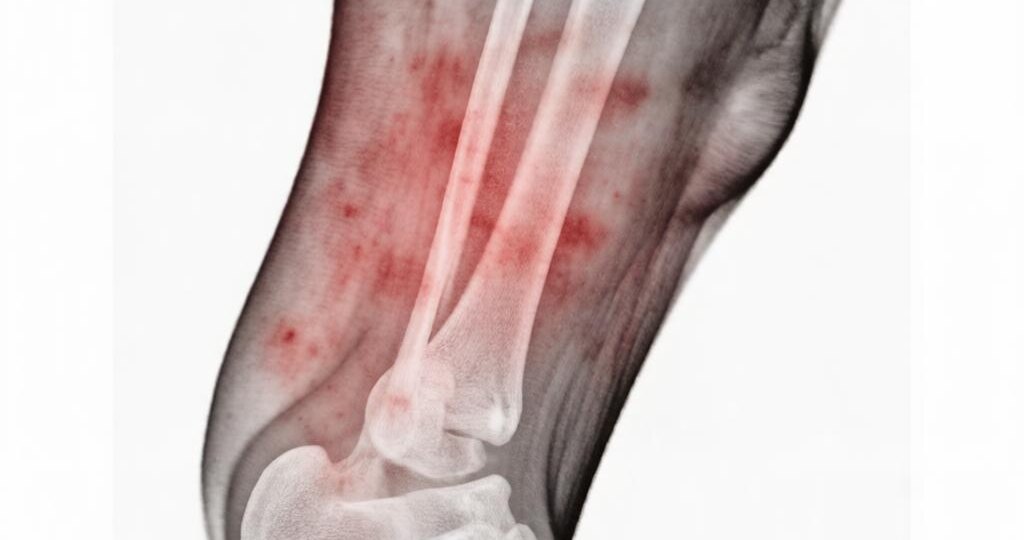

Когда пациент слышит диагноз «подагра», его мир делится на «до» и «после». «До» — это сочные стейки и копчености на завтрак, «после» — страх перед каждым куском и пуриновыми таблицами в телефоне. Особенно остро проблема стоит утром. Организм обезвожен после ночи, концентрация мочевой кислоты в крови максимальна, а есть хочется не пресную кашу на воде, а что-то, что вернет вкус жизни. Как врач, я часто вижу крайности: либо жесткую голодовку, которая провоцирует кетоацидоз и новый приступ, либо срыв на запрещенные продукты. Я подготовил для вас 5 рецептов завтрака, которые находятся в «зеленой зоне». Это блюда с низким содержанием пуринов, противовоспалительным потенциалом и отличным вкусом. С точки зрения метаболизма мочевой кислоты, молочные продукты с низкой жирностью — наши лучшие союзники. Молочный белок (казеин и сывороточные альбумины) обладает урикозурическим эффектом — он стимулирует выведение мочевой кислоты почками. Забудьте о жирной деревенской сметане. Нам нужен зерненый тво